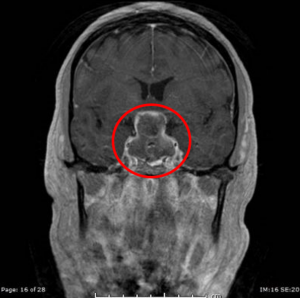

Die Abbildung zeigt die Planung zur Entfernung eines Cavernoms des Hirnstamms mit Hilfe der Augmented Reality und die intraoperative Darstellung. Das Cavernom konnte komplett entfernt. Die durch die Blutung entstandenen neurologischen Ausfälle haben sich nach der Operation komplett zurückgebildet.